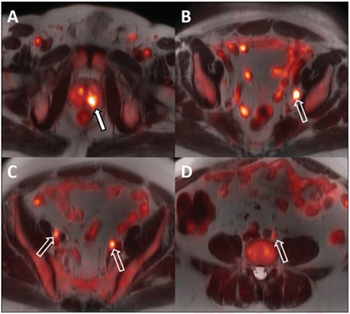

18F-fluciclovine PET/MRI can improve treatment guidance with better staging and evaluation of androgen deprivation therapy.